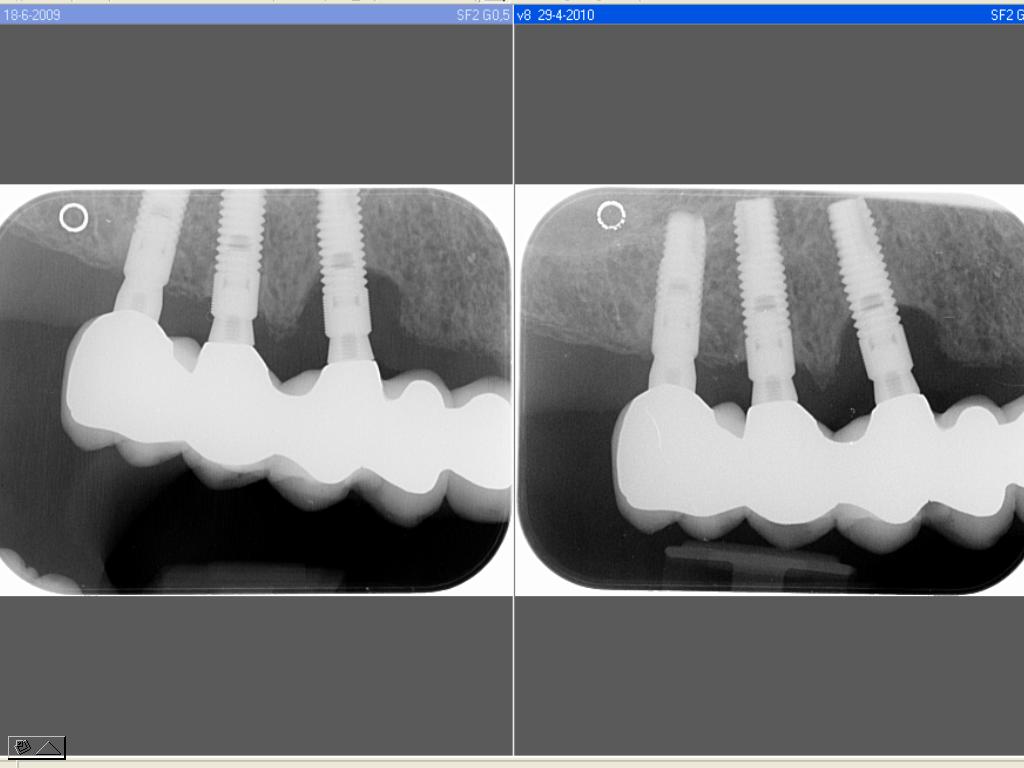

peri implantitis

Peri-implantitis

Belangrijkste kenmerken: • verticaal en/of angulair botverlies rond het implantaat • toename van de sondeerdiepte • bloeding na sonderen • pusformatie • roodheid en zwelling van de peri-implantaire mucosa • pijn en mobiliteit (In een laat stadium)

> sonderen van pockets ( ≥5mm, afhankelijk van de mucosadikte en abutmenthoogte) sonderen van aanhechtingsniveau (verlies van aanhechting) > bloeden na sonderen > pusvorming > meten van recessie > mobiliteit > meten van botverlies (röntgendiagnostiek) > bepalen van pathogenen (microbiologische diagnostiek)